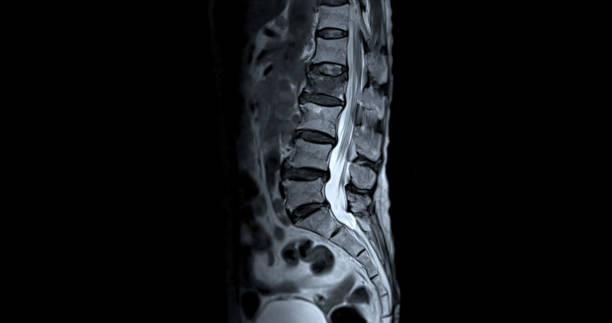

허리디스크는 많은 사람들에게 고통을 주는 흔한 건강 문제 중 하나입니다.

이 글에서는 허리디스크를 낫게 하는 데 도움이 되는 요추 전만 자세를 정리합니다.

요추 전만 자세의 중요성

요추 전만은 허리디스크 치료와 예방에서 핵심적인 역할을 합니다. 요추 전만을 만들면 디스크의 압력이 감소하고 허리디스크 증상을 완화할 수 있습니다. 이를 위한 두 가지 자세가 있습니다.